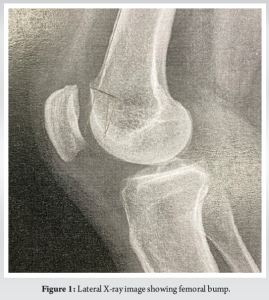

- Radiographs showed complete bone healing and restored slope (Fig. 5).